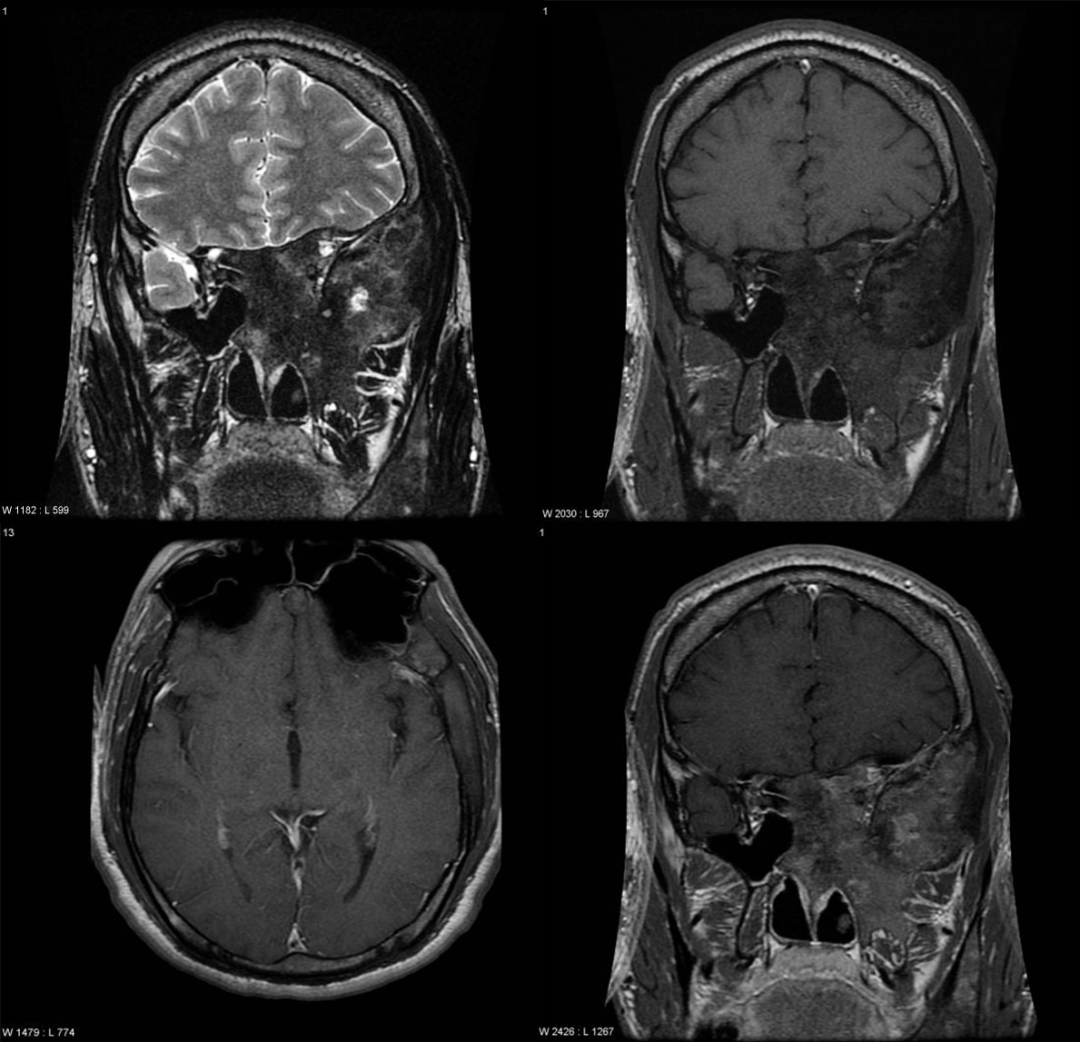

注:颅底骨(颞骨鳞部、右侧蝶骨体、蝶骨大翼、右侧筛窦壁)膨大,呈磨玻璃样改变,右侧翼管、圆孔变窄。T1WI 呈低信号,T2WI 呈低信号,增强 T1WI 呈轻度不均匀强化。

病灶内信号变化与病灶内成分相关,T1WI: 通常为等信号,也可为低信号或混杂信号;T2WI: 通常较低,但可能有信号较高的区域或混杂信号区域;T1WI+C(Gd): 呈不均匀增强。

(注:双侧顶骨板障不均匀增厚,T1WI 呈等、低信号,T2WI 呈稍低信号,增强 T1WI 呈轻度不均匀强化。)